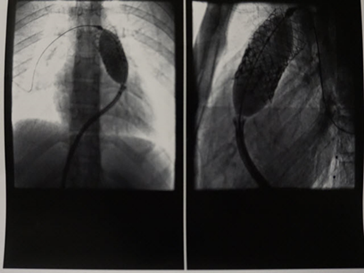

On June 13, 2016, James Kyser, M.D., of the Pediatric Cardiology Center of Oregon, became the first and only pediatric cardiologist in the state to provide the Edwards SAPIEN XT transcatheter heart valve procedure for pulmonic valve replacement to pediatric patients. This procedure took place just two months after the FDA approval.

The SAPIEN XT valve enables Dr. Kyser to treat his pediatric patients who suffer from congenital heart disease without having open heart surgery. This minimally invasive procedure provides a treatment option for a group of patients who typically face multiple open-heart surgeries, often times beginning at birth or during childhood. As risks increase with each open-heart surgery, a non-surgical option can help them receive treatment, recover and return to normal activities sooner. The procedure is done in the catheterization lab and allows for the valve to be inserted in a vein in the hip and then moved up to the heart and expanded to its full size.

Dr. Kyser has been working with a smaller valve, the Melody transcatheter pulmonary valve, since 2011. The Melody valve only reaches up to 22 mm. The SAPIEN XT valve, which reaches 29 mm, allows Kyser to extend care to a larger population, being used in children as small as 40 pounds up to adults. “Many of my patients will have or have had multiple surgeries over their lifetime,” said Kyser. “With the SAPIEN valve, I can now provide a minimally invasive surgery option that allows them to go home the next day and get back to normal activities within a week. “Before the SAPIEN XT valve, most of his pediatric patients would be referred to surgery, resulting in longer recovery times. Now, they may not require a valve replacement or surgery for 10-15 years.